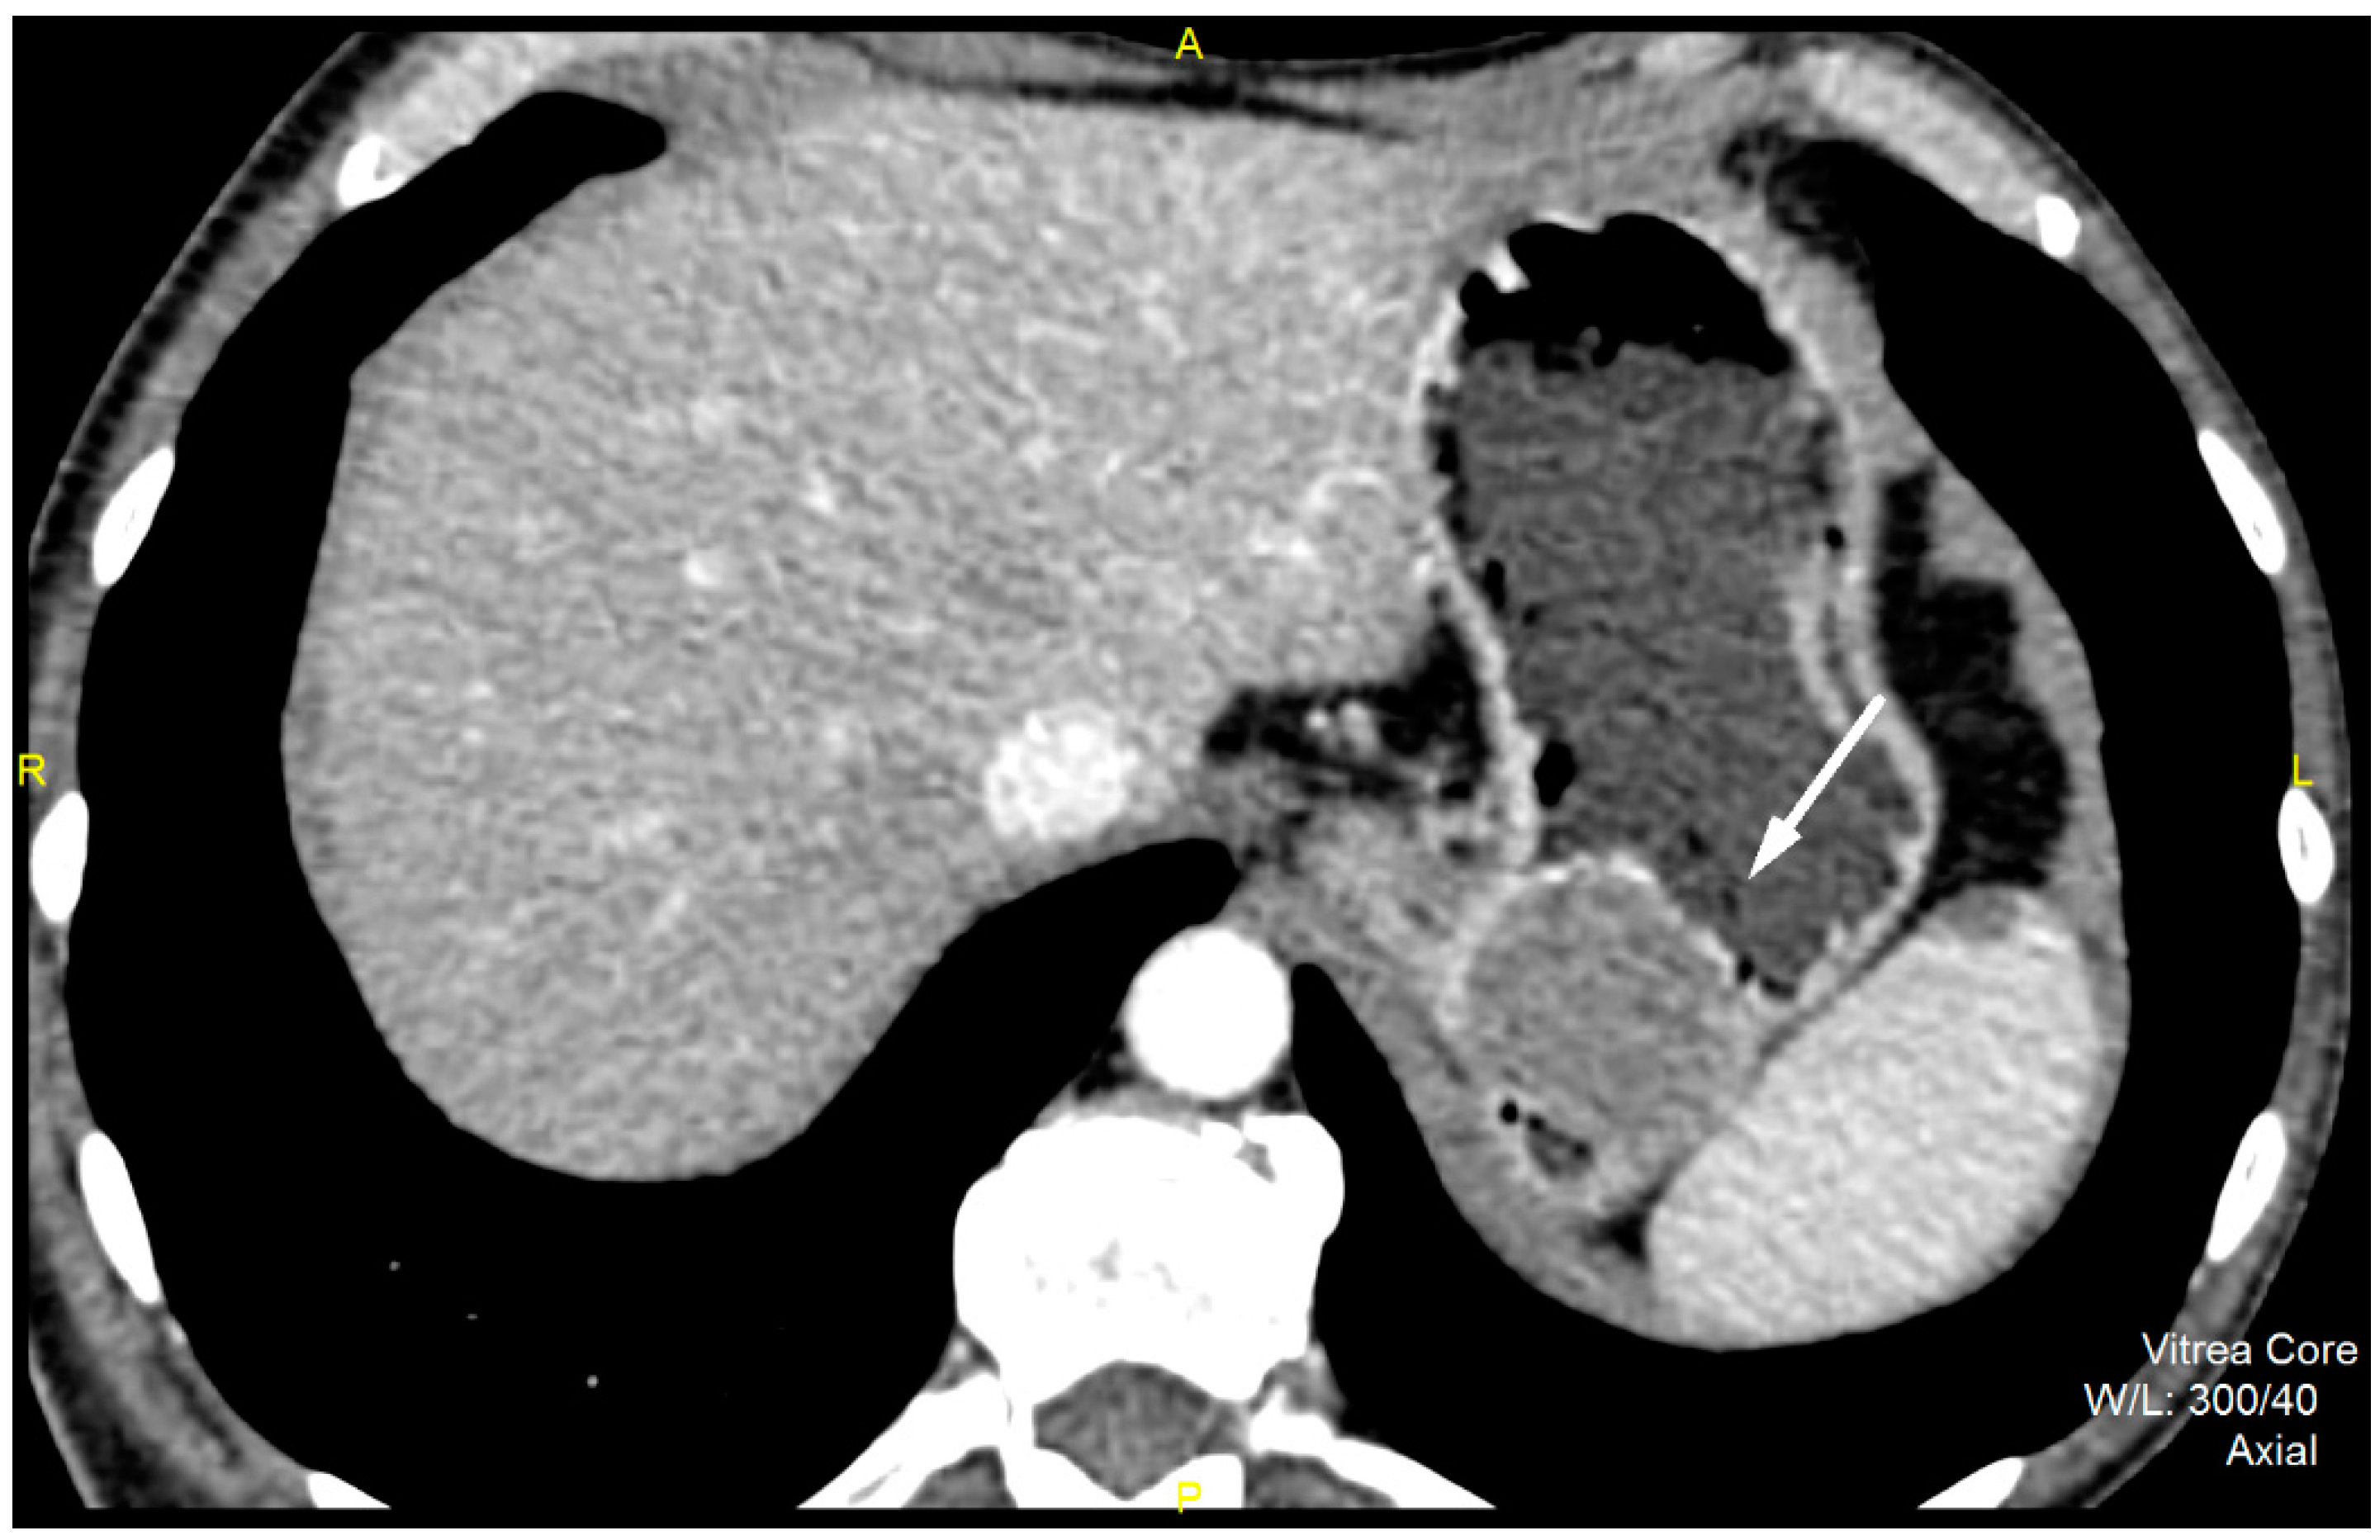

Figure 1.

Contrast enhanced computed tomography of the abdomen, axial view, demonstrates low grade GIST (white arrow) in a 54-year old male patient as submucosal, with a round lesion with endophytic growth in the subcardial region of gastric body. The tumor has an approximate diameter of 45 mm, a solid structure with low post-contrast opacification, covered by an intact mucosa.